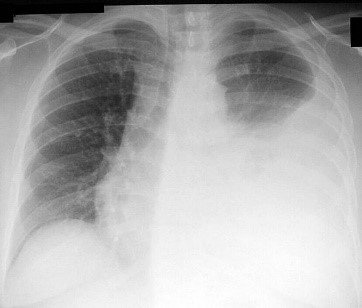

A pneumothorax is a collapsed lung and occurs when air leaks into the space between the lung and chest wall. Tension Pneumothorax is especially deadly.

Tension pneumothorax is a life-threatening condition that can develop when either the visceral pleura is disrupted, or with injury to the tracheobronchial tree. Rapid, accurate diagnosis and appropriate therapy are required to prevent significant atelectasis, hypoxia, circulatory arrest, and possible patient death.

Healthcare providers struggle to assess the success of decompression due to a lack of any immediate objective feedback. The gaseous composition of tension pneumothorax is similar to that of end respiratory gas. This includes an increased partial pressure of carbon dioxide in comparison to atmospheric air, which makes colorimetric capnography an ideal confirmatory test.